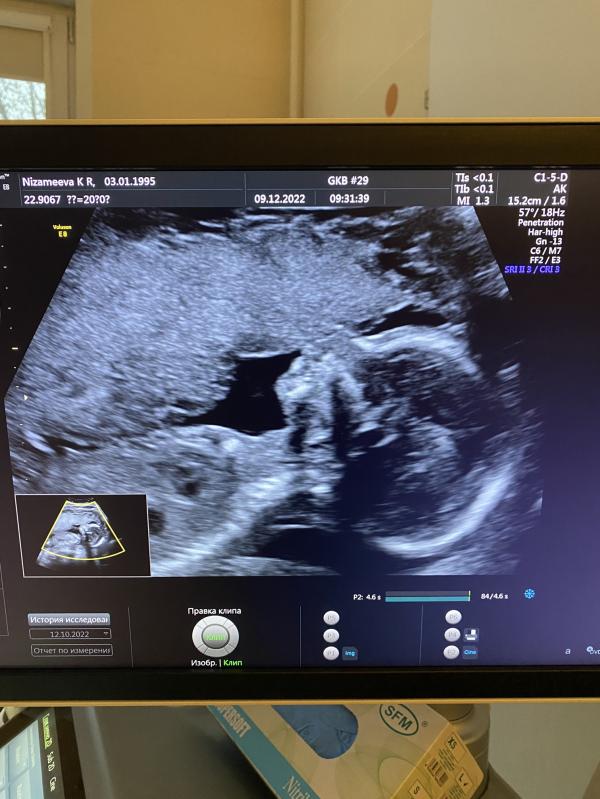

Так вот сегодня я лежу на скрининге и прошу просто подтвердить пол малыша знаю что девочка ну так просто , чтоб подтвердили уже точно) и тут мне говорят у вас мальчик

Точно говорит узист и показывает в стороне писюн ( но я ничего уже не вижу не понимаю ) где там писюн 😆

Ну девочки я все таки через месяц схожу ещё на узи и посмотрю ) как раз с мужем а то бесплатно с мужем не пускают ) смогла только сфоткать его с экрана )